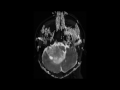

Choroid Plexus Papilloma

In this 3-year-old male with new onset symptoms of obstructive hydrocephalus, there is a circumscribed T1-isointense mass arising within, enlarging, and obliterating the fourth ventricle on the first image. Image 2, which is an axial FLAIR demonstrates a mildly hyperintense mass with several flow voids predominantly along the periphery of the lesion. The mass extends through and enlarges the foramen of Lushka on the right. There are no suspicious findings on the DWI or ADC maps, images 3 and 4, respectively. A small focal cystic region is identified along the posterolateral aspect of the lesion on the right. The presence of numerous flow voids, representing enlarged and tortuous feeding arteries, is confirmed on image 5, an axial T2-weighted sequence through the posterior cranial fossa. Image 6, a postcontrast sagittal T1-weighted sequence through the posterior cranial fossa demonstrates avid enhancement of the lesion. Choroid plexus papillomas, which are considered WHO grade I, make up about 3% of intracranial tumors in children. Greater than 80% of these lesions are identified in patients less than 5 years of age. The most common location choroid plexus papillomas are identified are at the trigone of the lateral ventricles. The lesions arise within the fourth ventricle more commonly in adults.